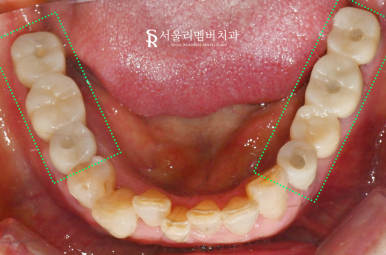

촬영일:2024.11.05

진료가 완료된 모습을

봉천동 치과 와 같이 확인하겠습니다.

스케일링을 통해

치석과 치태를 먼저 제거했습니다.

그 후 치근을 발거하고

임플란트와 브릿지를 통해

자연치를 대체했습니다.

더불어 치관이 마모되고

오래된 보철에 문제가 생겼던 곳도

자연치를 살려서

지르코니아로 덮어씌워

보호해 주었습니다.